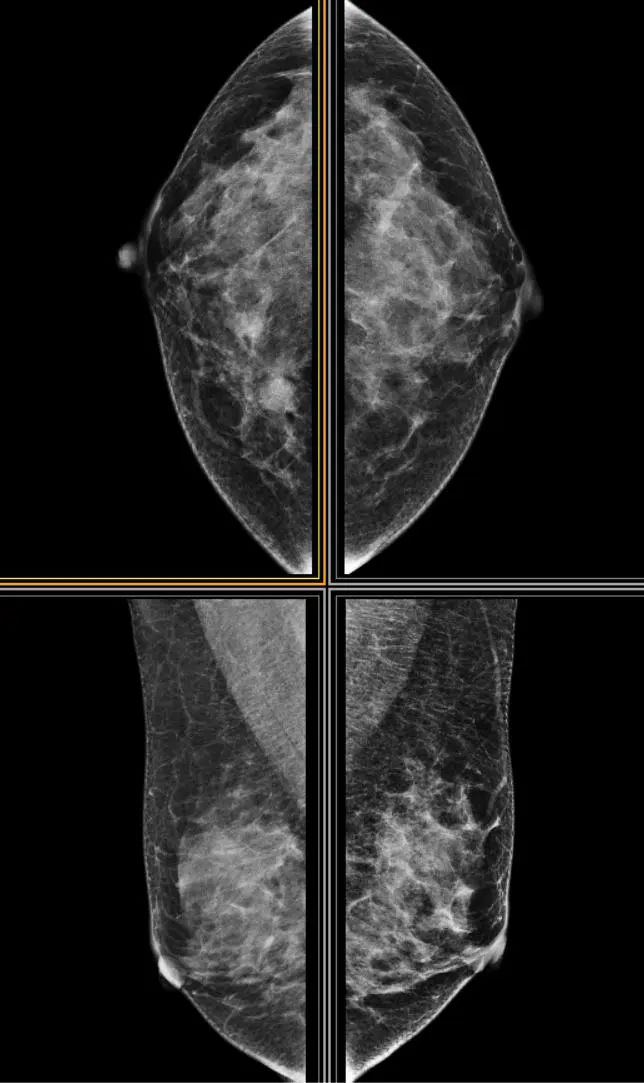

乳腺X线(钼靶)

摄影检查乳腺X线摄影是检查乳腺的最基本的影像学方法,具有较高的灵敏度和特异度,常作为乳腺疾病检查的首选,是乳腺疾病的普查和乳腺癌筛查的重要手段。其基本原理是利用乳腺组织对软X线穿透进行投照,再利用胶片进行感光,进行感光并成像。现市面所使用的X线摄影机主要有计算机X线摄影(CR)、数字乳腺X线摄影(DM)、乳腺的数字化断层摄影技术(DBT)等几大类,其中CR及DM已被广泛应用于临床。

优点:简单、方便、费用低、无创、诊断标准完备;尤其对早期乳腺癌微细钙化成像清晰、特征突出,是公认的检测早期乳腺癌的有效手段;方便观察肿块、钙化、不对称、结构扭曲等。

缺点:易受患者乳腺腺体类型、乳腺形态及病变组织位置的影响,易产生假阴性,造成漏诊或误诊。其对乳腺的良恶性病变鉴别时,钼靶摄影有时定性不准,易造成诊断不准确。对于X线摄影不能显示或定性不清的肿瘤,还需借助其他影像检查。有微量辐射,不推荐孕期及哺乳期女性做。